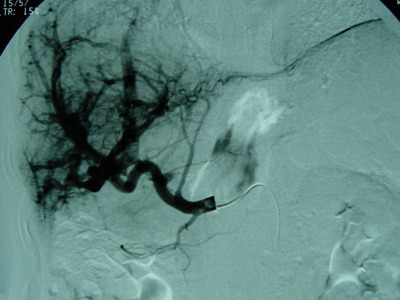

肝动脉、肠系膜上动脉、脾动脉造影见肝总动脉明显增粗,动脉期肝动脉及其分支显影良好,动脉早期可见门静脉显影,呈明显肝动脉—门静脉双轨征。肝实质期未见肿瘤染色。肠系膜上动脉间接门静脉显影,门静脉主干显影。门静脉血流方向为双向。可见胃底曲张血管逆行显影。